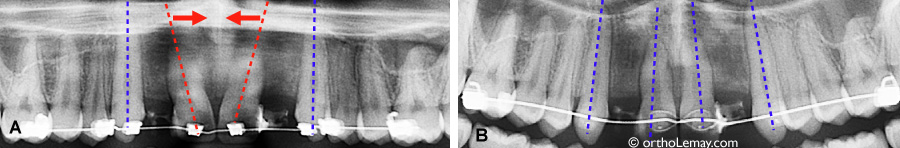

(A) Parallélisme de racine et espace inadéquat entre les racines pendant le traitement d’orthodontie. (B) Après quelques mois, les racines sont parallèles et il y a assez d’espace pour la pose d’implants dentaires dans les espaces édentés.

La position trop inclinée des incisives centrales supérieures empêchera la pose d’implants dentaires pour remplacer les incisives latérales manquantes. (A) Avant le traitement : les flèches bleues indiquent les incisives latérales manquantes. (B) Ces incisives latérales sont remplacées par des dents prothétiques collées aux dents adjacentes. (C) Une radiographie panoramique confirme la mauvaise position des incisives centrales. (D) Vue agrandie de la radiographie et implants ajoutés comme simulation. Les pointillés bleus représentent la position idéale que devraient avoir les incisives centrales. (E) Cette patiente a opté pour une technique de broches linguales pour des raisons esthétiques.